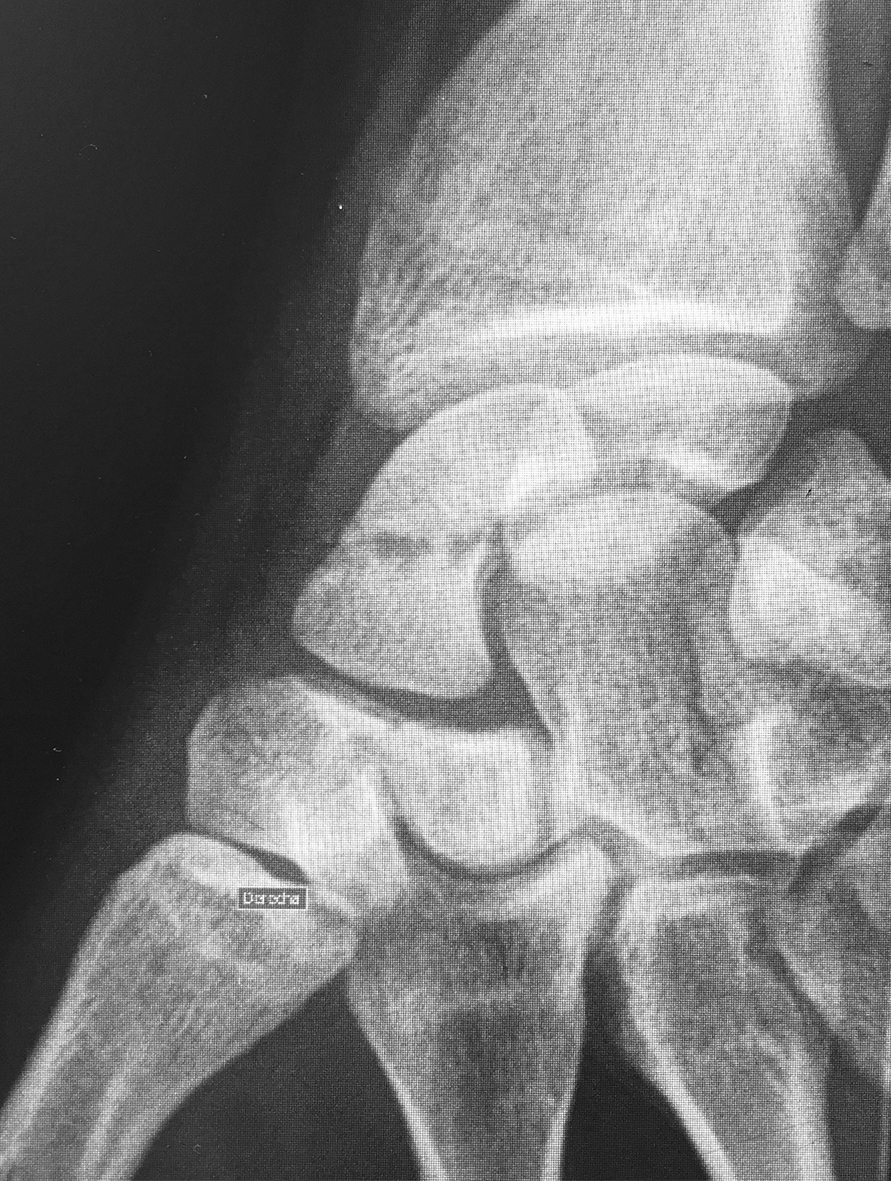

Figura 4: Caso 12

c) Radiografía post operatoria

e) 24 meses de seguimiento. Radiografía de frente

f) 24 meses de seguimiento. Radiografía de perfi